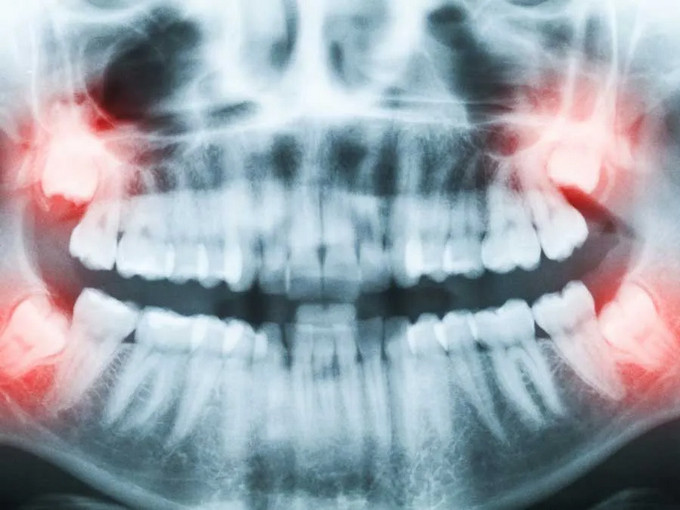

不少患者因埋伏牙、阻生牙饱受牙龈肿痛、牙列拥挤等问题困扰,但又因担心手术疼痛、创伤大而迟迟不敢治疗。事实上,埋伏牙不及时处理,不仅会反复感染,还可能损害邻牙、影响口腔健康,甚至引发囊肿及颌面部间隙感染等严重问题。

♢智齿阻生,频繁发炎疼痛

♢埋伏牙致邻牙病变或囊肿风险